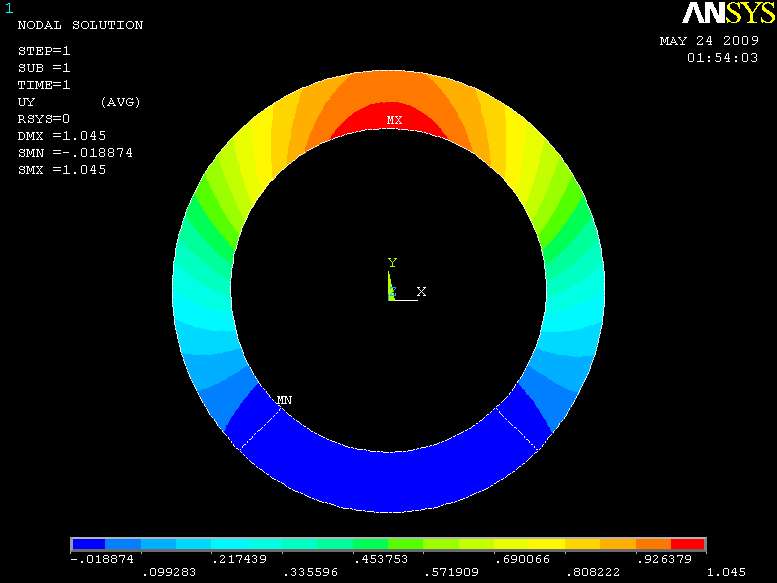

In case of plane strain, the problem at hand can be simplified as follows. Assume that we have an inhomogeneous ring cylinder with a known height. Since the foundation of our research is based on the assumption of plain strain/stress, there is no strain/stress along the direction and therefore the cylinder’s height doesn’t have any effect on the solution. The assumption of an inhomogeneous ring cylinder is because of the changes occurred in the mechanical properties of heart muscle after introducing infarction. After defining the elastic properties of the ring cylinder, the structure is ready for the next step which is loading. In this step the load is applied in a uniform and radial manner inside the ring, to mimic the process of loading the heart muscle. The internal pressure applied to the ring is time varying. Fig.3 represents the results of ANSYS analysis of the ring for displacement in , and the absolute values of displacements respectively.

After the analysis with ANSYS, the proposed model should be implemented and the results should be compared and verified with the results of ANSYS analysis. At first the inner and our contours of the ring is determined. Then, after setting the boundary conditions, the governing equation of deformation is solved using FEM and the deformation maps are created. All the code is implemented in MATLAB.

Fig. 4 represent the results of the proposed method for both horizontal, vertical and absolute displacement. To better be able to compare the results, the ring is divided into 16 sub-regions and the results of ANSYS and MATLAB implementations are compared. Fig. 5 shows the average displacement in each region for 10 iterations of pressure increment for both ANSYS and proposed method. Based on the provided results, it can be seen that the proposed model is consistent with the results of ANSYS, even in regions with low mobility (regions 11, 12, 13 and 14).